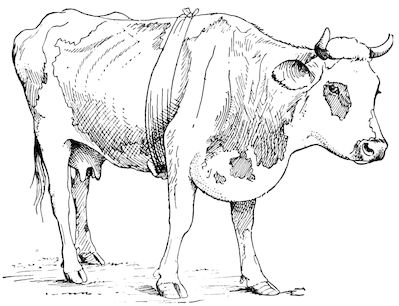

Fig. 2.—Horse suffering from osseous cachexia.

2. The second phase is characterised by more precise signs, which become almost pathognomonic. Difficulty in rising is added to the already existing tendency to remain lying, and to the interference with movement.

When lying down the patient no longer responds to the trifling stimulus, which a healthy animal needs to cause it to rise. It remains languid and apparently lazy, though in reality it experiences pain and difficulty on attempting to get up. The least muscular effort when lying down often causes it to moan, as do efforts to change its position or to walk. Even when standing still, it may appear to be in pain, and patients often assume a position similar to that of a horse suffering from laminitis.

At the end of this second phase, swellings appear, due to synovitis or arthritis of the extremities, synovitis of the sesamoid or navicular sheaths or to inter-phalangeal arthritis or arthritis of the fetlock joint. Weakness becomes marked, and the appetite is very irregular.

10Secretion of milk diminishes or ceases and abortion is not uncommon.

3. The third phase is characterised by fractures, and it is this peculiarity of the disease which has procured for it the names of fragilitas ossium, and osteoclastia. These fractures may affect any portion of the skeleton. Animals so suffering sometimes break a leg whilst trotting or the pelvis in simply jumping over a ditch; a collision with a fixed object like the jamb of the stable door, or a fall on the ground, may result in the fracture of one or several ribs.

Fig. 3.—Pig suffering from osseous cachexia (fourth stage).

Such shocks would be of no importance to a healthy animal, but to one suffering from osseous cachexia, any violence, or even the slightest muscular effort may be followed by fracture of the gravest character, involving even the vertebral column. In cows the pelvis, femur, and tibia are most frequently injured.

In horses, particularly in riding horses, fractures are commonest in the region of the forearm, cannon bone, and anterior phalanges. So extremely fragile are the bones at this stage that the horse represented herewith broke twelve ribs at one time by simply falling on its side. It is interesting to note that such fractures are never accompanied by any extensive bleeding. They have little tendency to repair, no real callus formation occurs, and on post-mortem examination one often finds the ends unconnected by temporary callus, worn, and rounded by reciprocal friction.

At this stage but under other circumstances, the animals show great reluctance to rise, remaining down for twelve to twenty-four hours without shifting their position. If forced to get up, they stand as though fixed in one position, the respiration and circulation become rapid, and they soon grow tired and fall.

Fig. 4.—Deformity of the face in the horse shown in Fig. 2.

The flat bones are particularly liable to this change, which is common to domesticated animals. The bones of the head are the first to suffer; later those of the pelvis. The lower jaw becomes swollen, particularly about the centre of the branches which may attain three, four, or five times, their normal thickness.

The depression in the submaxillary space disappears. The upper jaw undergoes similar changes, becoming deformed and thickened until the cavities of the sinuses and the hollow appearance of the palate are lost, while the face is so changed that it cannot be recognised as that of a horse, goat, etc.

The molar teeth are almost buried, their tables alone being visible at the bottom of a depression, the edges of which rise above the neighbouring parts (pig).

Mastication is clearly impossible, the jaws appear paralysed, the muscles powerless, and only swallowing is possible, a fact which explains why life is only prolonged to this stage in animals which can be fed with a spoon or bottle (pigs and goats). The bones of the cranium, although greatly changed in texture, are always less deformed than those of the face.

The changes are such that it is often easy with a mere post-mortem knife to cut the head completely in two. Osseous tissue, properly so-called, has disappeared.

All the constituent tissues, with the exception of the skin and muscles, i.e., the bone, periosteum and aponeuroses, have the appearance and consistence on section of the fibro-lardaceous tissue seen in chronic inflammation.

The following is a condensed description of the disease as given by Law:—

Symptoms. Poor condition or even emaciation, with very visible projection of the bones. The coat is rough, skin tense, inelastic and 12hidebound, appetite variable, sometimes impaired, and nearly always perverted (or depraved) so that the patient will lick the manger continually or pick up and chew all sorts of objects: bones, leather, clothing, wood or iron, stones, etc. The amount of food consumed may, however, be up to the normal. The most marked feature is the difficulty and stiffness of locomotion.... Temperature and yield of milk may remain normal.

“Later, appetite and milk secretion fail, temperature rises a degree or two, the animal refuses to rise, remaining down twelve to twenty-four hours at a time, and ... when rising ... remaining on the knees for a time, moaning and indisposed to exert itself further. At this stage many cases begin to improve and may get well in five or six weeks. Some will remain down for several weeks and finally get up and recover. With constant decubitus, however, the animal falls off greatly, becoming emaciated and weak, the appetite may fail altogether, and the patient is worn out by the persistent fever, nervous exhaustion and poisoning from the numerous bed-sores ... which are common over the bony prominences. It is in these last conditions, above all, that fractures and distortions of the pelvic bones, and less frequently of the bones of the legs occur.”

Fig. 5.—Head of a pig suffering from osseous cachexia.

“The disease may advance for two or three months, and in case of pelvic fractures and distortions, there may be permanent lameness, and dangerous obstruction to parturition, even though the bones should acquire their normal hardness through the deposition of lime salts.”

In horses, the different phases of the disease develop precisely as in bovines. The apparent differences between affected horses and cattle result in reality from differences in their capacity for continuing work. In the first phase, horses are incapable of work, their movements being 13badly co-ordinated. They are inclined to stumble, and appear as though suffering from strain of the lumbar muscles.

In the second phase pain referable to the bones sets in. Lameness develops without visible lesions and is rapidly followed by synovitis and arthritis in the lower portions of the limbs, and by wasting and anæmia.

The animals seem unable to move rapidly, or if forced to do so may sustain fractures even at a trot: the limb bones sometimes break or ligamentous insertions in the neighbourhood of joints are torn away, resulting in sudden falls on the ground and fracture of ribs or even of the vertebral column. This corresponds to the third phase, osteoclastia, in oxen.

Fig. 6.—Osseous cachexia. This condition developed in two months, the last month of gestation and the first of lactation.

From then onwards, horses become useless and, if not destroyed, may, after a few weeks or months, develop the condition known as osteomalacia, in which the flat bones become softened, the head, the branches of the lower jaw and the face become deformed, while mastication and other functions are impeded.